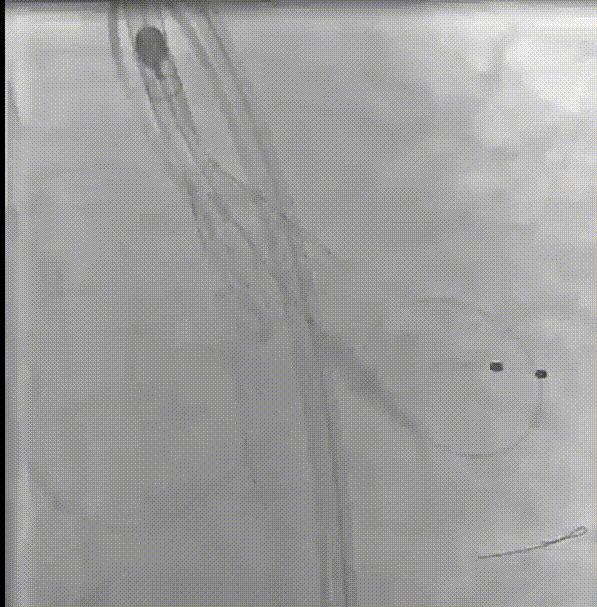

术中操作

支架预埋

瓣膜首次定位释放

瓣膜释放至2/3

回收瓣膜再释放

多体位下观察植入深度

释放完成